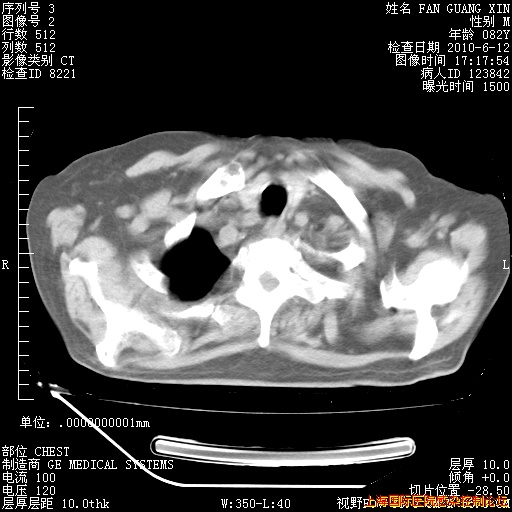

6月12日肺窗

6月12日纵膈窗